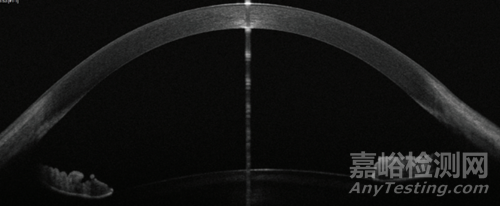

成像效果對比:

▲ArcScan Insight 100 成像結(jié)果

▲OCT成像結(jié)果

ArcScan Insight 100獨(dú)具的尺寸定型功能可輔助臨床醫(yī)生在應(yīng)用實(shí)踐中最大化降低與ICL尺寸相關(guān)的并發(fā)癥風(fēng)險(xiǎn)?;贗nsight 100針對眼內(nèi)后房的直接測量結(jié)果,為患者選取最精準(zhǔn)適宜的人工晶體。系統(tǒng)通過生成液晶級“HD”超清精顯圖像(對比其他超聲生物顯微鏡系統(tǒng)的“模擬化”成像效果),確保角膜層面的測量精度保持在1.0 µm以內(nèi),虹膜后的側(cè)向測量精度則在0.12 mm以內(nèi)。